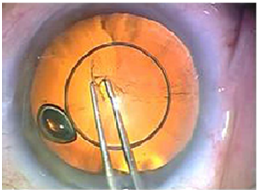

Many different methods has been described to perform CCC;10 in general the technique starts after filling the anterior chamber with viscoelastic and puncture of the anterior capsule using a cystotome or a 23 gauge sharp needle and continue the tear in a circular fashion with a forceps clockwise or counterclockwise all the way around to the starting location (Figure 1A&B).

Figure 1 (A) Schematic representation of CCC. (B) In vivo CCC with trypan blue.